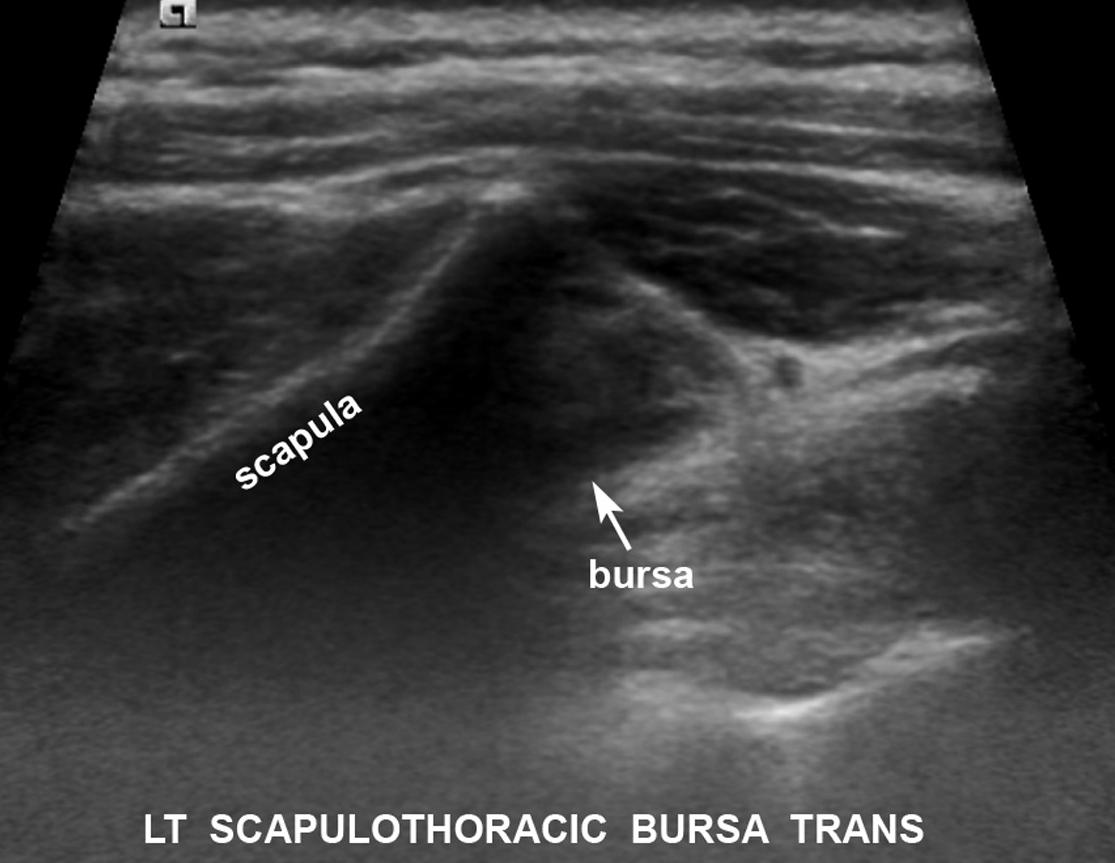

Ultrasound Guided Scapulothoracic Bursa Injection in a 32 Year Old

Scapulothoracic Bursa Ultrasound . when the arm is flexed behind the back (b), a small amount of fluid is visualized in the scapulothoracic bursa. scapulothoracic bursitis and crepitus remain primarily clinical diagnoses; scapulothoracic crepitus is the presence of a grinding or popping sound with movement of the scapula that may or may. scapulothoracic bursitis and the snapping scapula syndrome is a rare condition caused by the disruption of the gliding articulation.